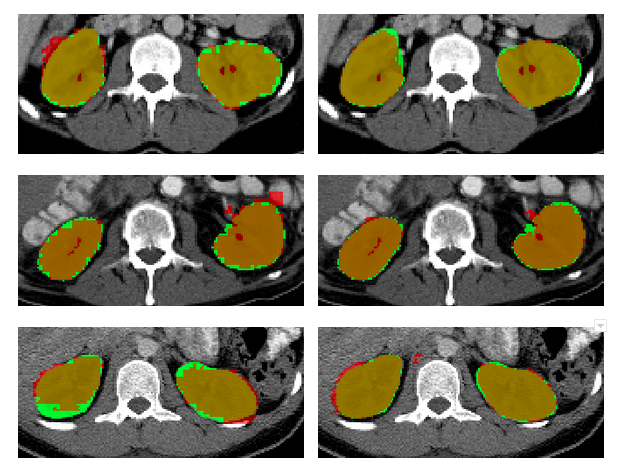

Refer to caption

Fig. 4: Sample segmentation results at the end of 200 epochs for 3 cases. Top to bottom: cases 1-3. Left to Right: results of models trained without (i.e. trained from scratch) and with self-supervision, overlaid on the ground truth. Green: Ground truth; Red: Prediction.

Fig. 4 shows the segmentation results of MwS, overlaid on the volume and ground truth. The segmentation results of MwoS overlaid on the volume, are compared on the right side. It can be seen that with MwS, the segmentation captures the fine structures as well without over-segmenting. In the case of MwoS, voxels towards the edges of the kidneys are seen to be misclassified as background while in some locations some over-segmentation can be observed.